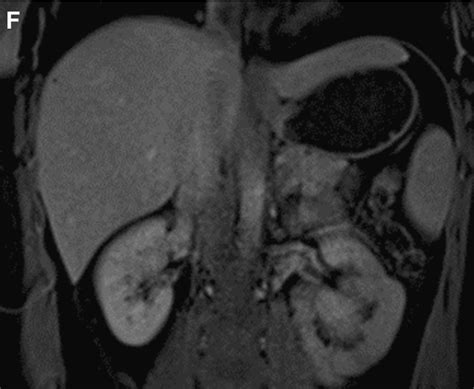

• Imaging Studies: Ultrasound, computed tomography (CT) scan, or magnetic resonance imaging (MRI) may be used to visualize the liver and surrounding structures. These imaging studies can help identify inflammation or other abnormalities.